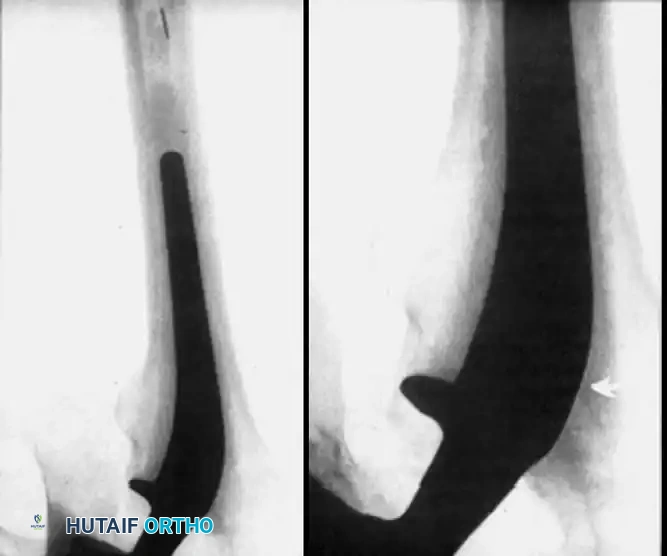

Associated Surgical & Radiographic Imaging